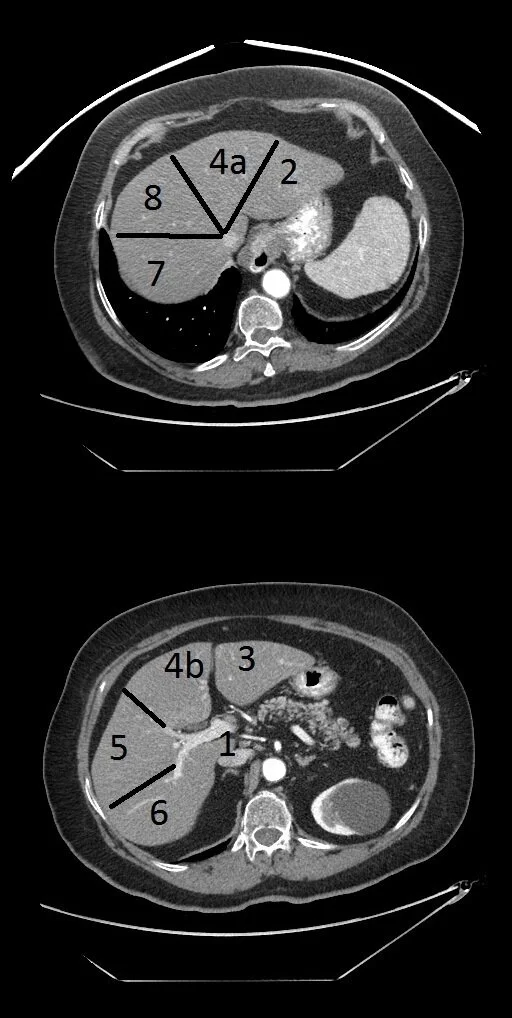

Hepatic Segment Numbering